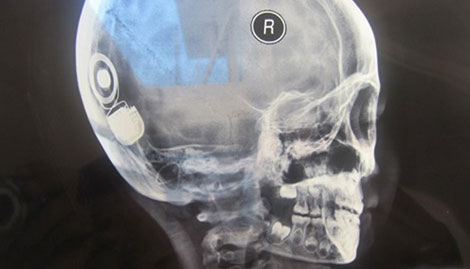

Ngày 29-4, Ths.Bs Phan Hữu Chính - Phó Giám đốc Bệnh viện đa khoa tỉnh Khánh Hòa cho biết, các bác sĩ khoa tai – mũi họng bệnh viện này vừa phối hợp đoàn bác sĩ của Bệnh viện Quốc tế City TP Hồ Chí Minh thực hiện thành công hai ca mổ, cấy ghép ốc tai điện tử cho hai bệnh nhi khiếm thính đầu tiên.